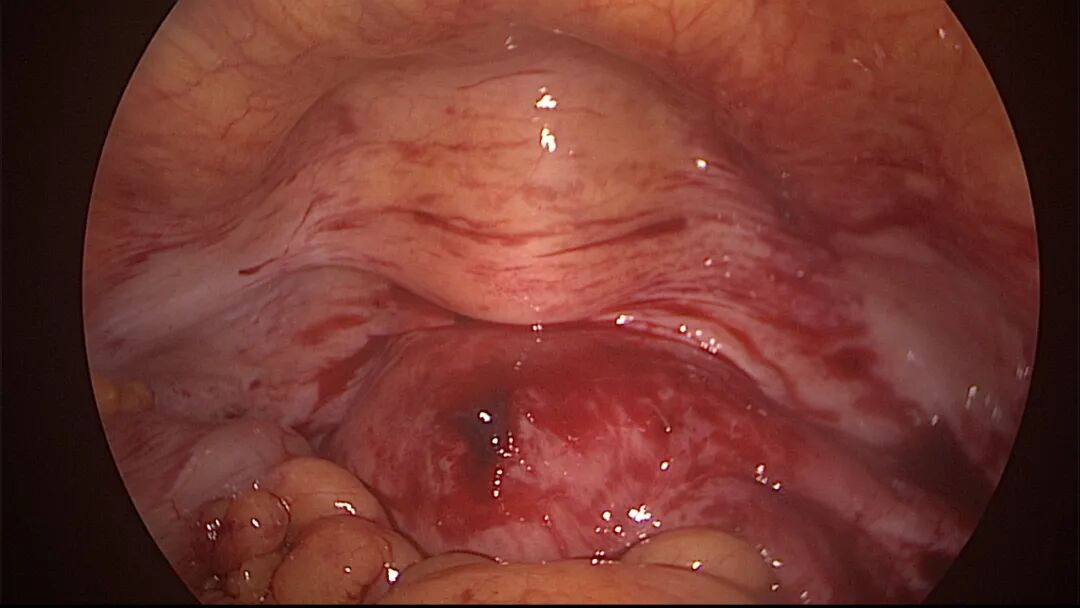

尽量保护输卵管开口周围内膜不受损伤,术中仅显露出左侧输卵管开口。该患者术后自然妊娠,34+周剖宫产分娩

个体化选择手术器械,减少内膜损伤及内膜丢失:冷刀优于能量器械,双极优于单级,电针优于电切环。能量器械设置最低有效能量,少用电凝。尽量避免探查宫深及扩宫操作,宫腔镜直视下进入宫腔,必要时采用阴道内镜方式进入,保持宫颈管及宫腔原始状态显露在宫腔镜下,不破坏病灶,便于准确诊断,精准手术。非要扩宫时,选择尖头扩宫棒,方便操作。宫颈外口狭窄或封闭时,可用尖刀片切开宫颈外口,必要时缝合牵拉宫颈再做切开,切口术后可不缝合。输卵管开口是精子和胚胎运行的重要关口,形态多样,开口周围颜色比内膜颜色浅(未被损伤的输卵管开口美兰不着色),粘膜平滑而薄,呈放射状。宫腔镜手术不要损伤输卵管开口,开口周围息肉、粘连等病变可以用微型剪、异物钳或电针处理,尽量不用电切环。宫腔镜微创理念牢记心中:手术要有助于生殖、有助于恢复月经、有助于减少粘连复发。术中保存完整手术资料,除了拍照,必要时开启摄像功能,录制手术视频,利于术后复盘手术过程,作为分析、学习、讨论、反思、提高等资料备用。